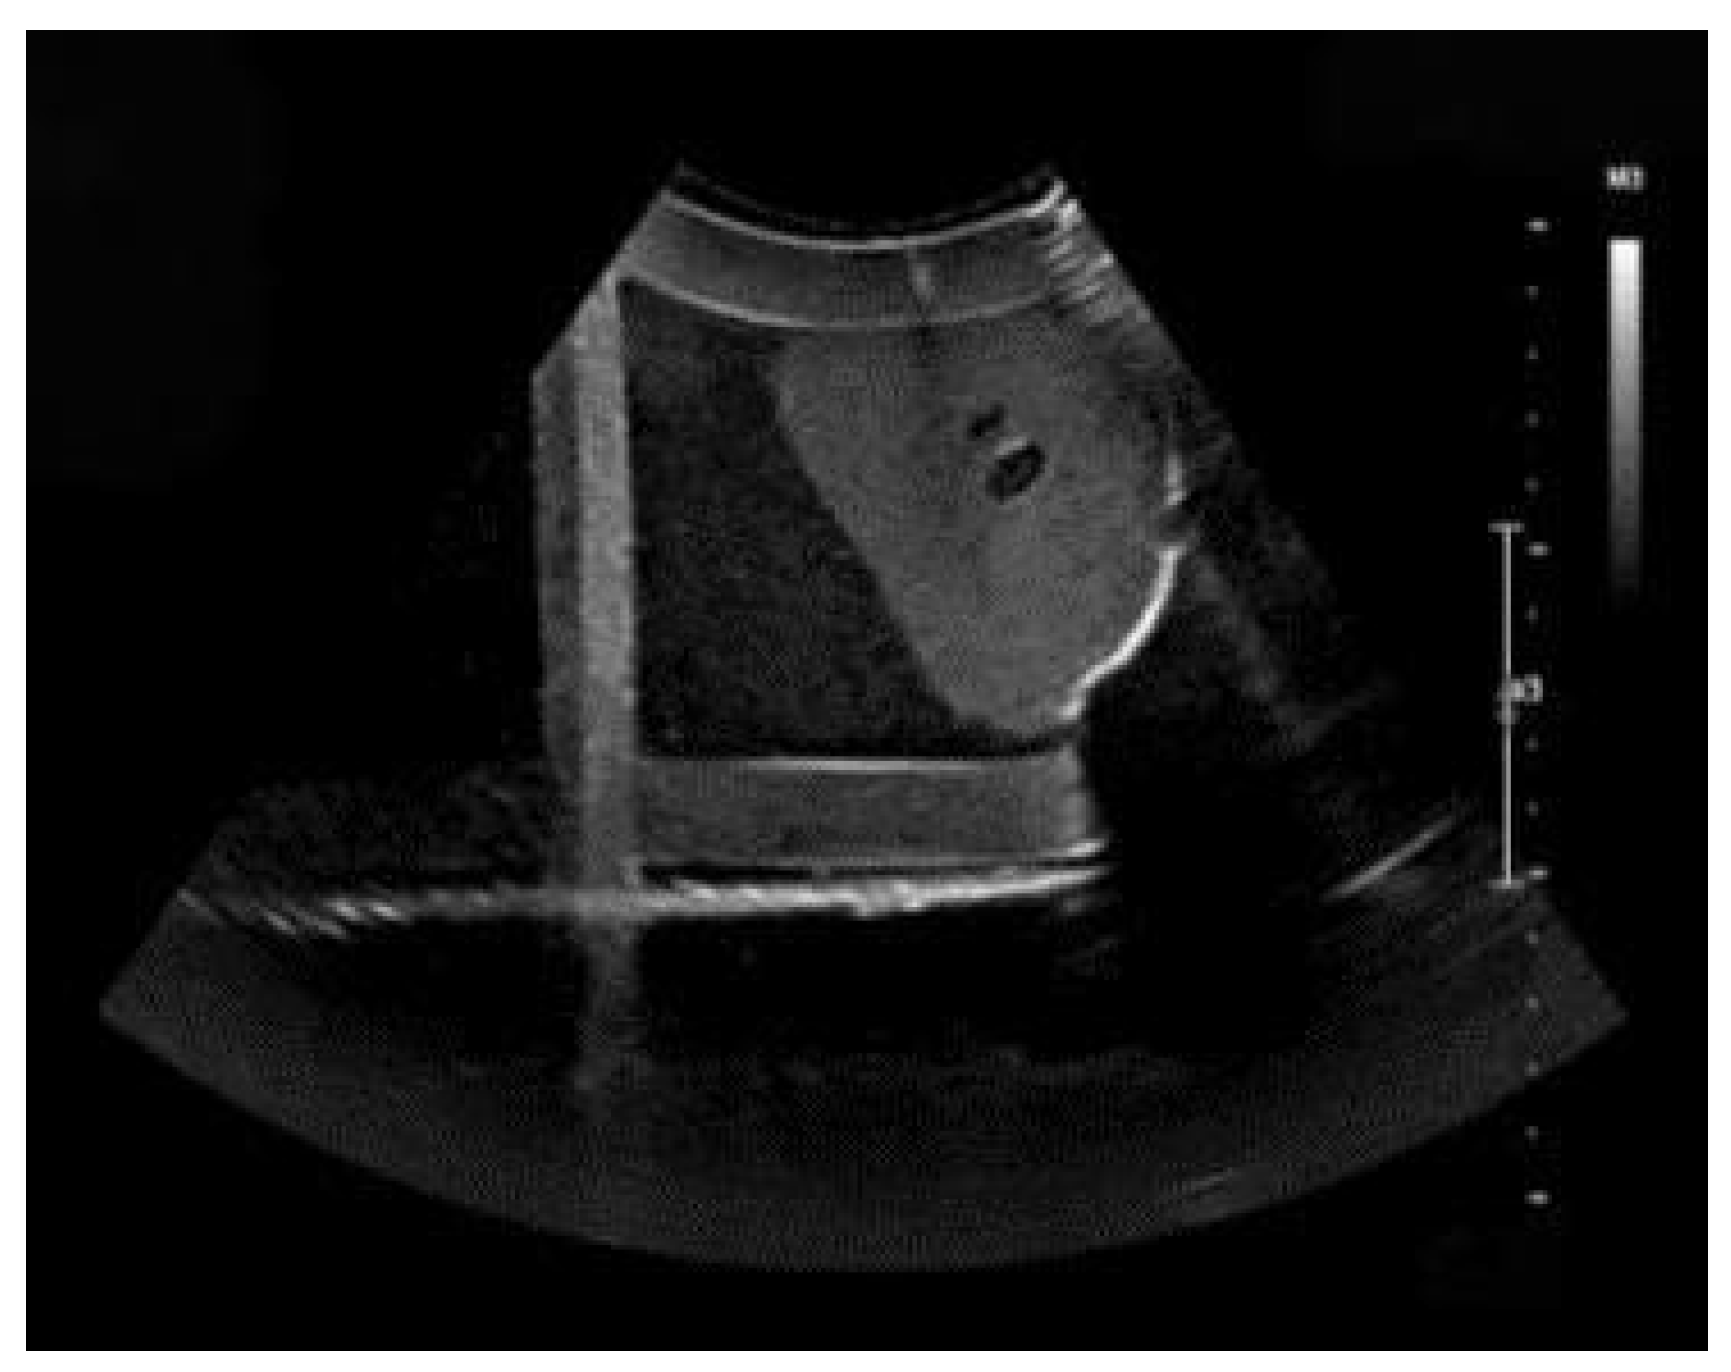

4.1. Three-Dimensional Reconstruction Results of Local Liver Ultrasound

4.2. Image Segmentation and Recognition Results